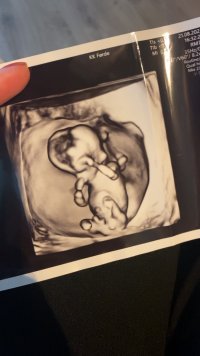

Her er ikke nub synlig dessverre13+4

Noen som snudde seg med ryggen opp, presset sammen som en liten ball inmerst i et "hjørne", så fort "kameraet" var på, så dette er dessverre det beste (og eneste) bildet.

Ja du har et poeng, jeg var litt usikker på denne, men syntes blæra satt så lavt. Blir spennende å hørehvor mange uker og dager? umulig å si ut i fra 3D bildene, men synes jo at dette ser ut som klitoris og kjønnslepper.

Bildene ble tatt 13+0hvor mange uker og dager? umulig å si ut i fra 3D bildene, men synes jo at dette ser ut som klitoris og kjønnslepper.

Jeg vil endre svare mitt, at det er en jente, jeg tror det er den hula rett bak nuben som er blæra ikke den litt nedenfor som jeg først tenkte.Bildene ble tatt 13+0

@lyse gul vil du gjette om det er jente eller gutt?Vet ikke om det er mulig å se en nub her?Jordmor ville/kunne vertfall ikke si noe - 14+0

har du flere bilder? synes ikke det er noe tydelig kjønnsorgan på disse.Vet ikke om det er mulig å se en nub her?Jordmor ville/kunne vertfall ikke si noe - 14+0